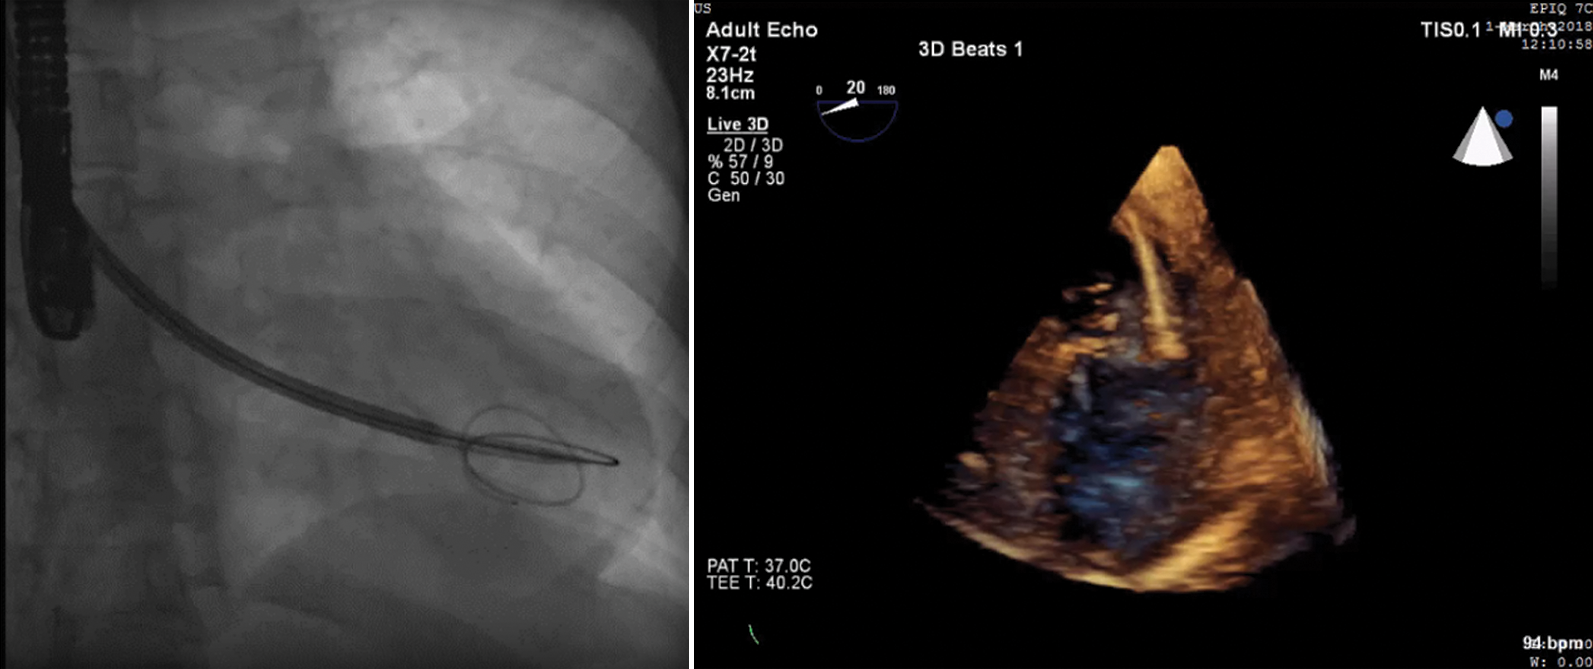

Hence, with the wire pointing toward the LV inflow, the mitral valve was successfully crossed under fluoroscopy and TEE guidance and the multipurpose catheter along with the steerable sheath were advanced in the LV (Fig. 3).

Figure 3: Fluoroscopy (left panel) and transesophageal echocardiography (right panel) images showing the 6 Fr multipurpose catheter and the Fustar Steerable Introducer sheath (Lifetech Scientific, Shenzen) advanced in the left ventricle